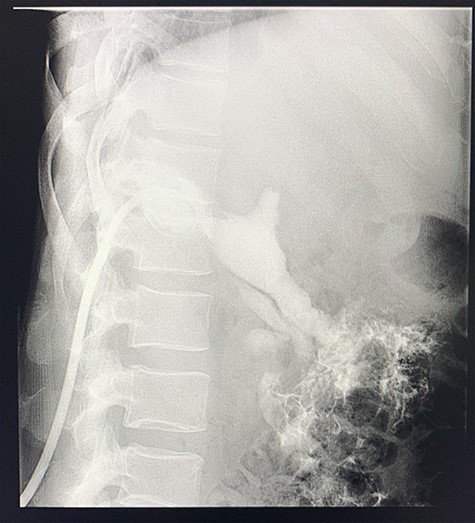

A computed tomography (CT) scan of the abdomen revealed an enlarged, thickened gallbladder with multiple stones, communicating with an intrahepatic collection in segment 4 measuring 116 × 80 mm, with an associated air fluid level and air locules (Fig. 1). There was an apparent fistulous tract to the hepatic flexure of the colon, another large collection in segment 6 (97 × 96 mm) as well as other smaller collections (Figs 2 and 3).

Axial view of portovenous phase of CT scan of the abdomen demonstrating enlarged, thickened gallbladder with radio-opaque gallstones with apparent fistulous communication with the hepatic flexure of the colon with associated pneumobilia.